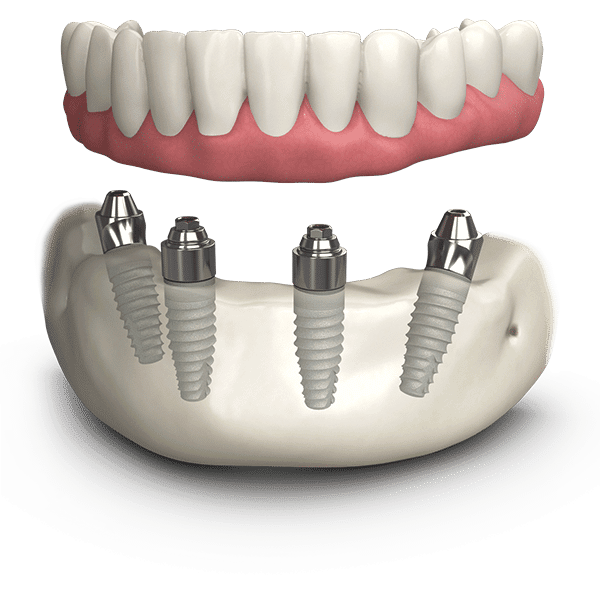

There are 2 main options for patients who want to replace a full jaw with new teeth. Both options require dental implants which act as the new tooth root to replace your missing teeth.

- A removeable denture that is supported by dental implants

In this case the dental implant is inserted into the gum which fuses to the jawbone and keeps it permanently in place. This acts as an anchoring support for the plastic set of teeth or dentures which sit on top.

- Fixed teeth supported by dental implants

In this option, the dental implant is inserted to the jawbone. An abutment then connects the implant with the dental crown which sits on top of the gum and shows as the tooth.

Dental implants are the only permanent, natural looking solution to replace a full set of teeth. If you are missing all teeth, several implants can be inserted into your jaw, which is then supported by a bridge to replace a full mouth of new teeth. Read on to find out more about these dental implant options.